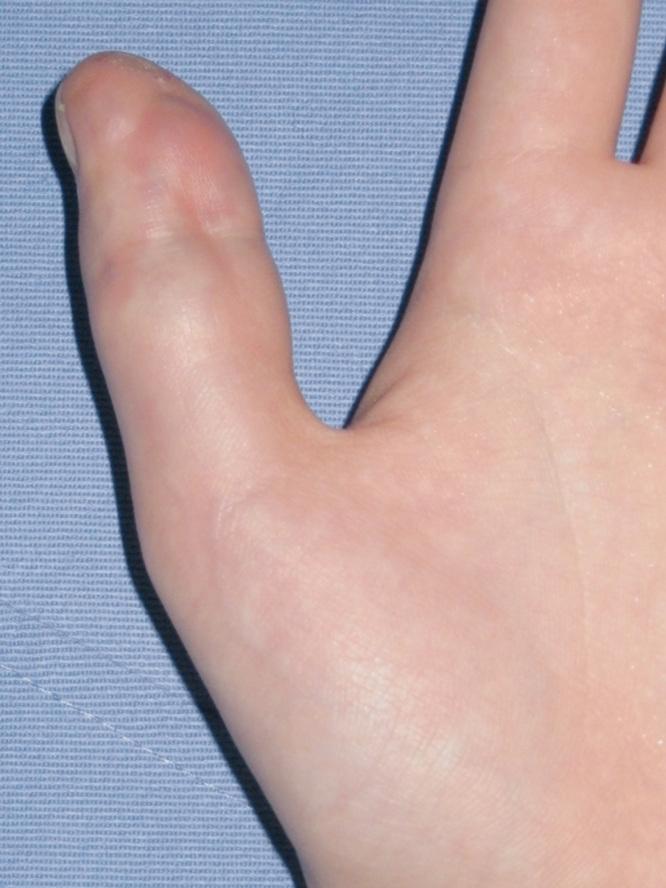

Vascular malformations of bone are complex lesions that can cause deformity and pain. A combined soft tissue and intraosseous venous malformation of the left thumb in a girl was treated with two sessions of ethanol sclerotherapy using a bone marrow aspiration needle under fluoroscopic guidance.

骨血管畸形是一种复杂的病变,可导致畸形和疼痛。一名女孩左拇指的软组织和骨内静脉联合畸形,在透视引导下使用骨髓穿刺针进行了两期乙醇硬化治疗。